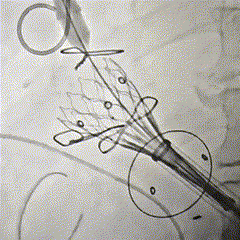

泥鳅导丝配合多功能导管跨二尖瓣,置入加硬导丝建立通路

瓣膜释放,位置良好

主动根部造影,冠脉显影良好,无漏

回收输送系统,撤出体外,无需造影,收紧荷包

Part3: EVAR

EVAR